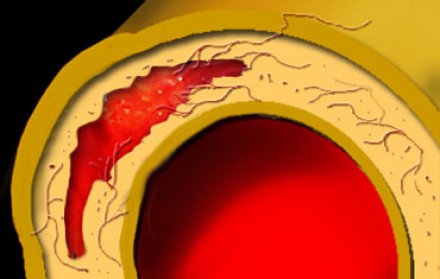

Пенетрирующая атеросклеротическая язва определяется как язва атеросклеротической бляшки аорты, проникающая через внутреннюю эластическую пластинку в медию. Такие поражения составляют 2-7% от всех случаев острого аортального синдрома. Распространение язвенного процесса может либо привести к развитию интрамуральной гематомы, ложной аневризмы, или даже разрыву аорты или расслоению аорты. Естественное течение этого заболевания характеризуется прогрессивным расширением аорты и образованием мешотчатой или веретенообразной аневризмы, что особенно быстро происходит в восходящей аорте (тип А ПАЯ). Пенетрирующая атеросклеротическая язва часто встречается в условиях выраженного атеросклероза грудной аорты, бывает множественной, и может сильно различаться по размеру и глубине поражения сосудистой стенки. Наиболее распространенной локализацией данной патологии является средняя и нижняя трети нисходящей грудной аорты (тип B ПАЯ). Реже, язвы находятся в дуге аорты или брюшной аорте, в то время как вовлечение восходящей аорты наблюдается редко. Общими чертами больных с пенетрирующей атеросклеротической язвой являются пожилой возраст, мужской пол, курение табака, гипертензия, ишемическая болезнь сердца, хроническая обструктивная болезнь легких, и сопутствующие аневризмы брюшной аорты. Симптомы могут быть аналогичны тем, которые имеются при диссекции, хотя они более часто проявляются у пожилых пациентов и редко манифестируют в виде признаков мальперфузии органов. Симптомы могут указывать на экстренную ситуацию при вовлечении адвентиции и возможном разрыве аорты. КТ является методом выбора для диагностики пенетрирующей атеросклеротической язвы на основании выпячивания контрастированной медии через кальцинированную бляшку.Основные факты:

Обширная кальцификация интимы и атеросклеротические бляшки.

Выпячивания контрастированной медии через кальцинированную бляшку.

Возможно контрастное усиление стенки аорты.

Продольно расположенная интрамуральная гематома.Ниже представлены типичные изменения, которые визуализируются на КТ при пенетрирующей язве аорты.